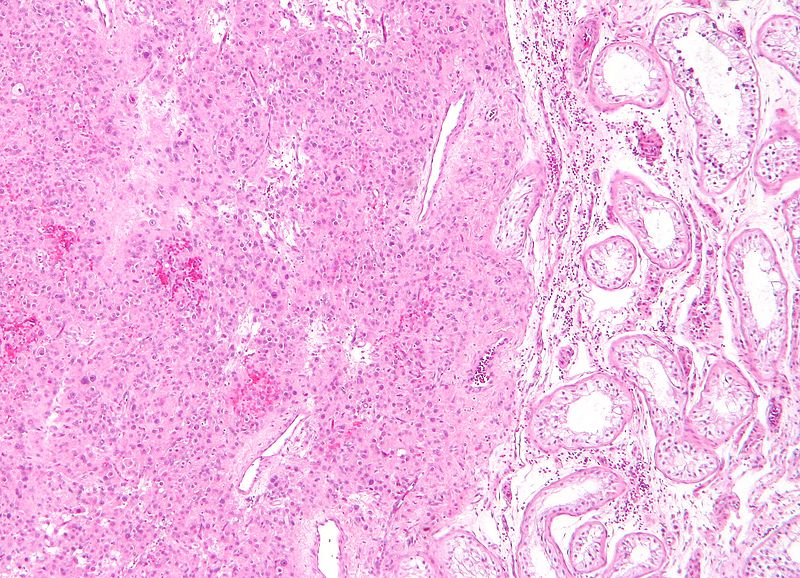

Large cells with transparent cytoplasm and central nuclei (like spermatogonia) make up the malignant tumor known as a seminoma, which develops as a homogeneous mass without bleeding or necrosis.

Histology of yolk sac tumors classically show Schiller-Duval bodies.

Characteristic Reinke crystals may be seen in histology of sex cord stroma tumors.